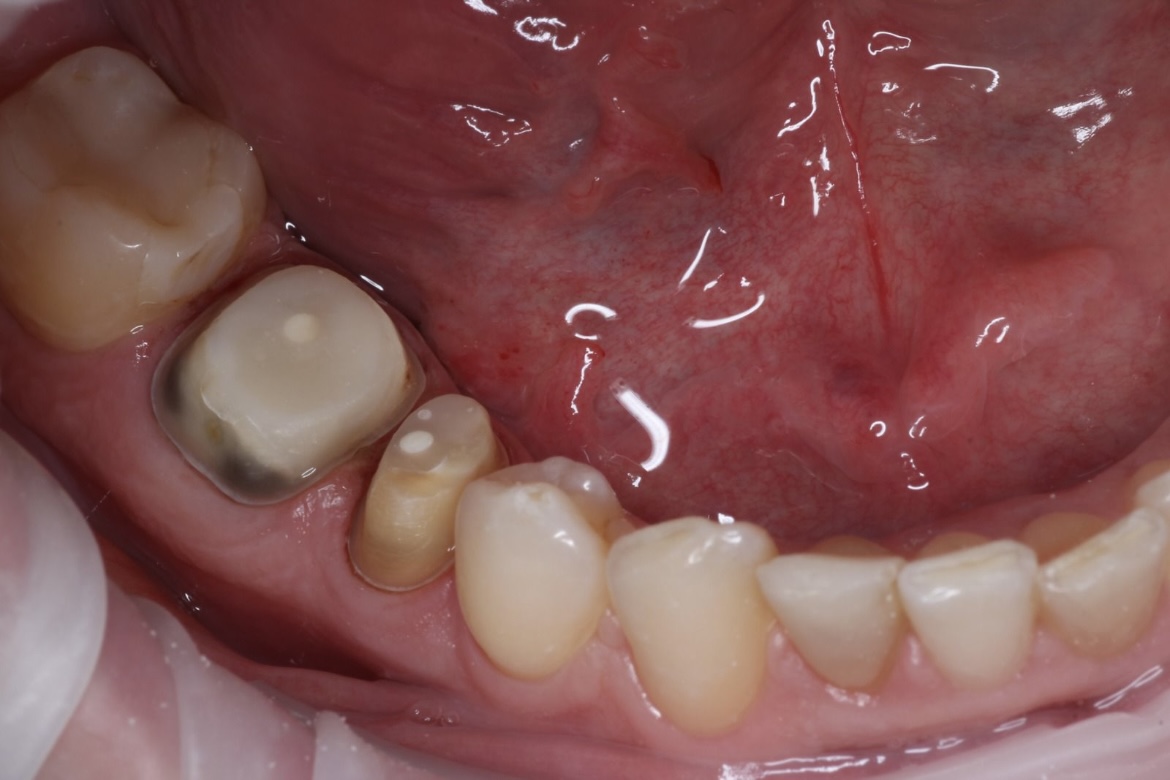

Наши работы